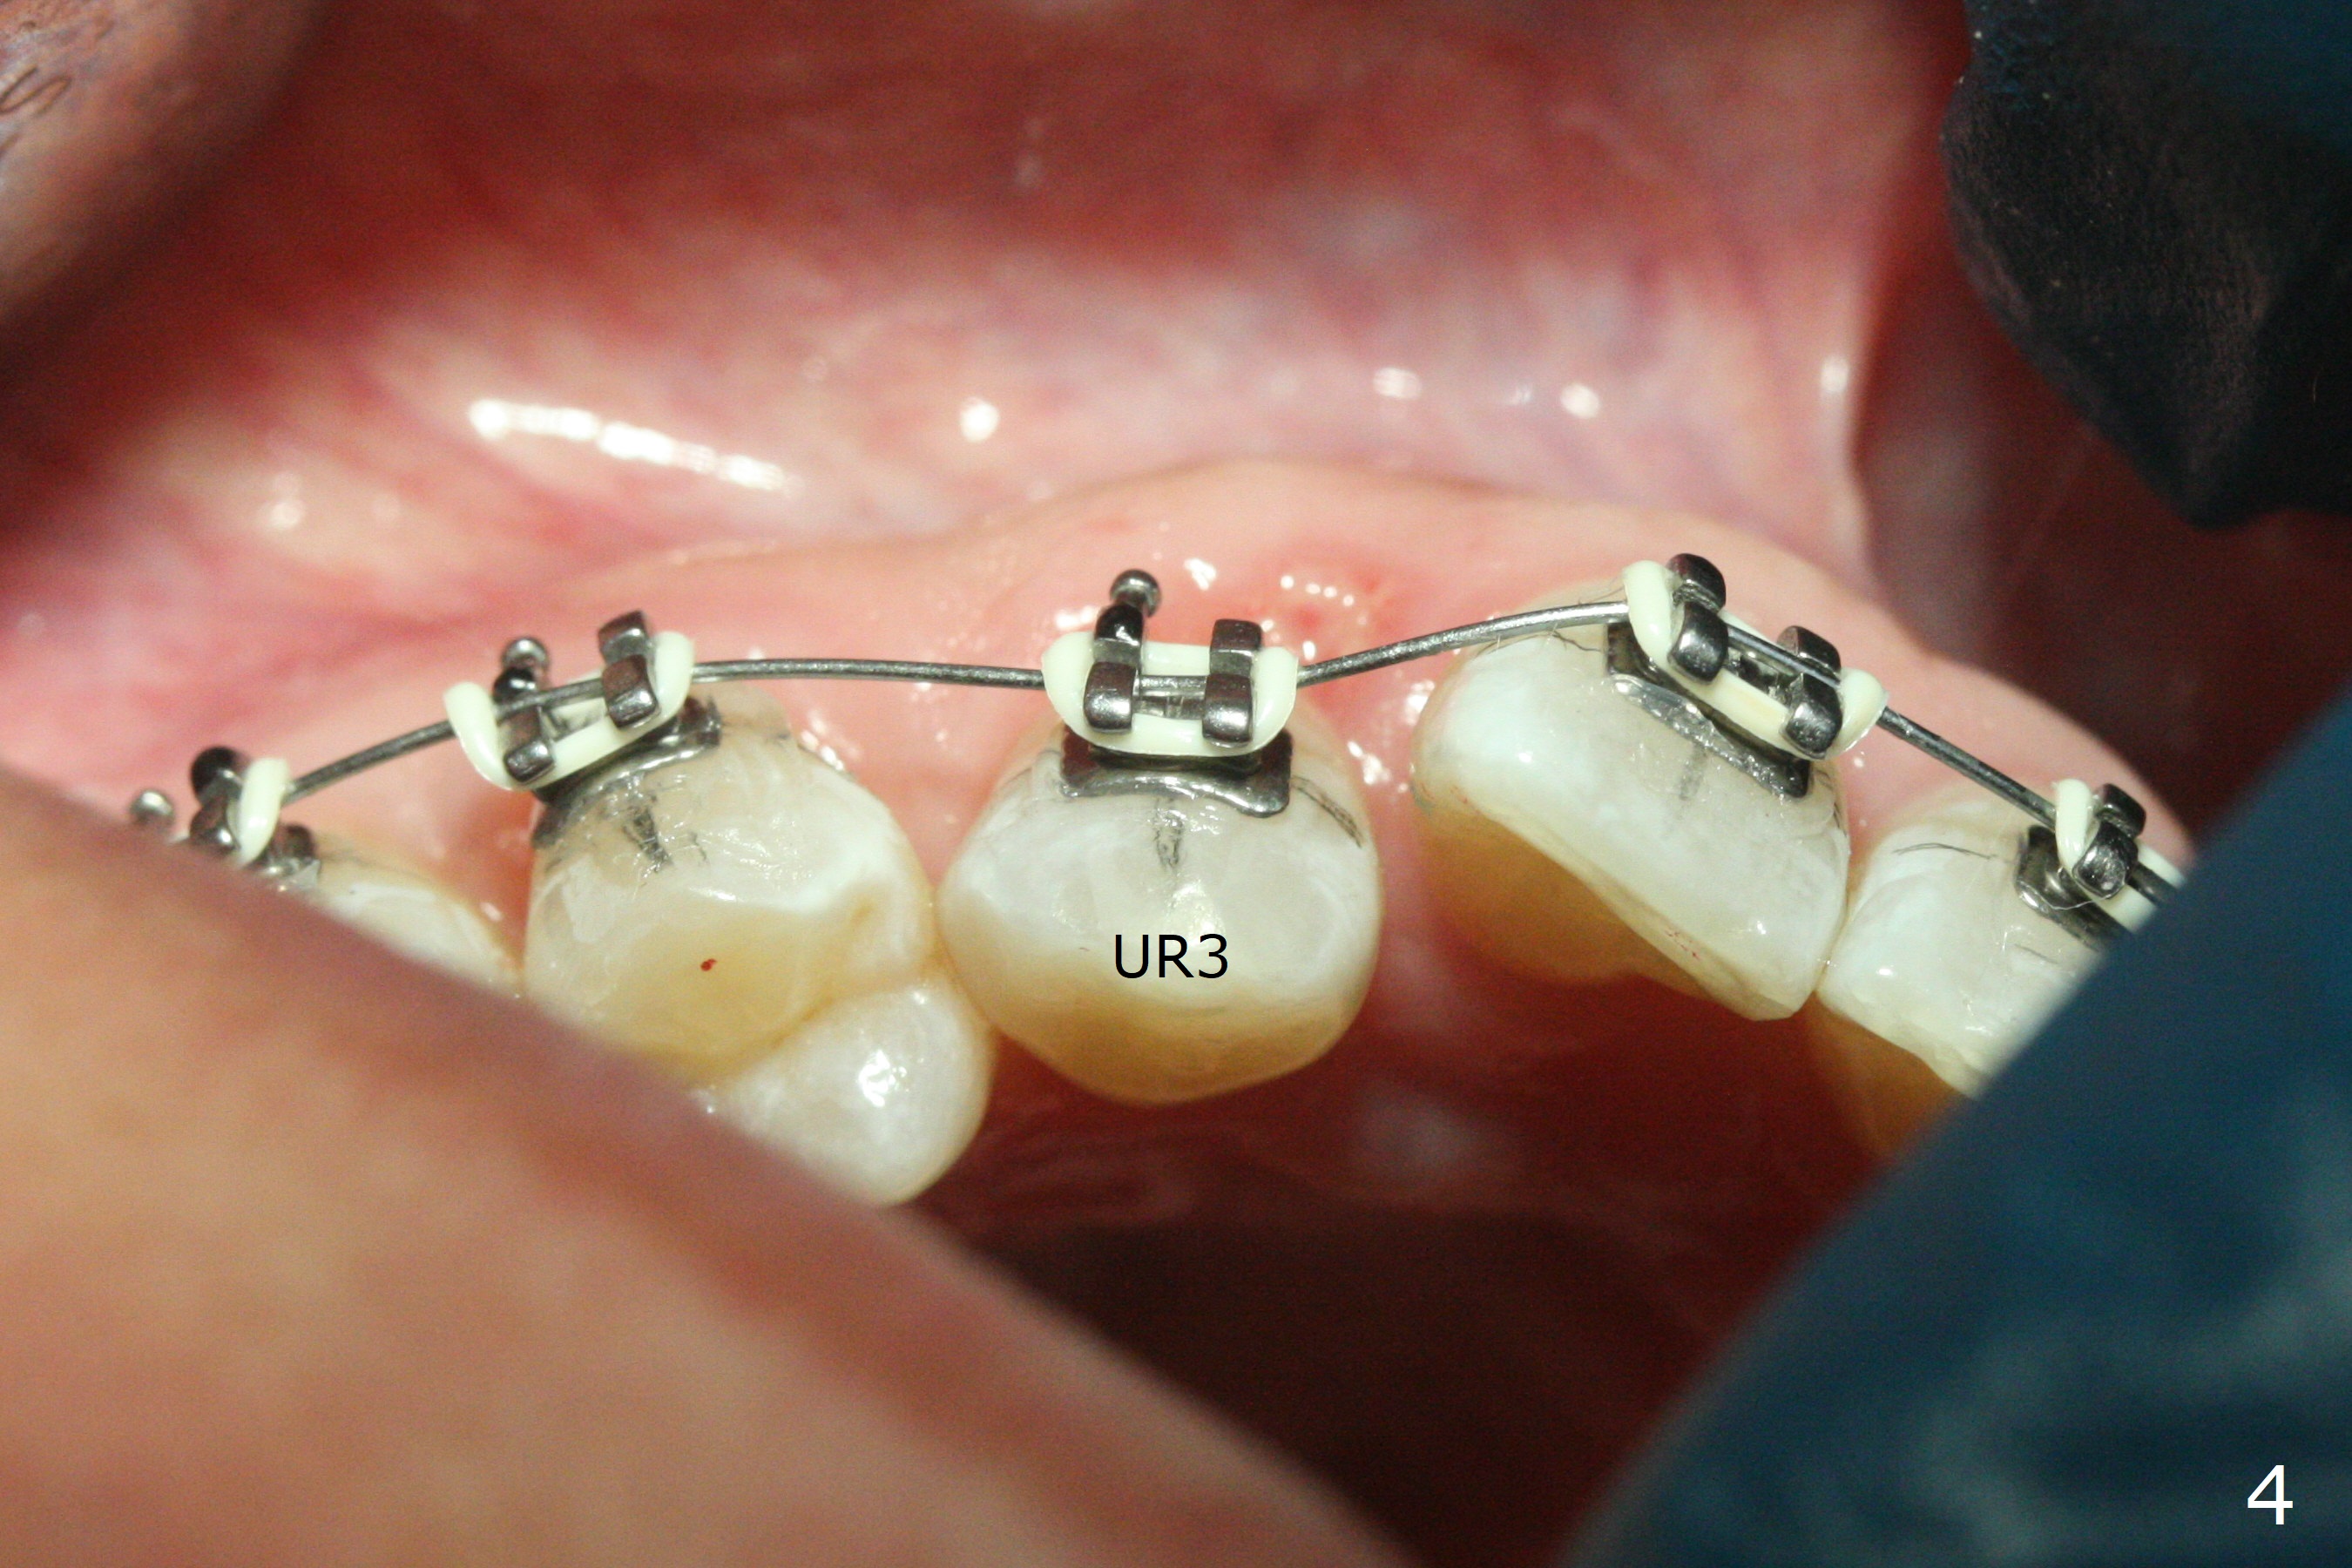

The 54-year-old woman returns for ortho-dontic treatment 1.5 months post extra-ction of UR2 (Fig.1,2). Brackets, bands and 14 niti wire are placed in the upper arch, whereas insufficient spaces are created for placement of the lower arch molar bands. Since there is no horizontal space issue, the cross bite canine is able to be corrected immediately when the vertical clearance is obtained (Fig.3,4). In fact composite is added to the 1st molars in a few days, since that in one of the 2nd molars dislodges. UR3 cross bite is nearly corrected < 2 months post banding (Fig.5), while brackets are placed in the lower arch (Fig.6 (coronavirus)). It appears that the lower arch will be too large when it is expanded for the upper one.